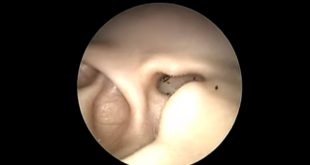

LEER MÁSTras fuertes dolores, extraen animal vivo del oído a paciente (VIDEO)

El otorrinolaringólogo Ranmat Omar, originario de Malasia, compartió en internet un video que grabó en el momento en que extrajo una garrapata viva de canal auditivo de un paciente. Según el doctor, el hombre acudió a consulta porque presentaba fuertes dolores en el oído interno y cabeza, sin imaginar que …